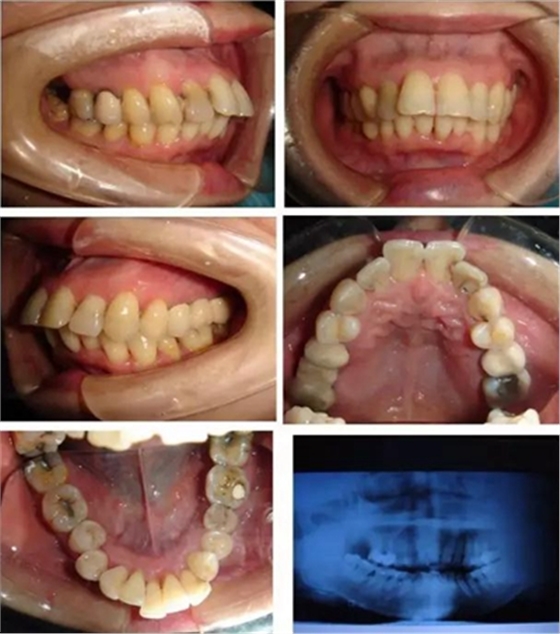

▲ 圖 輕中度患者骨性前突患者

選擇骨性雙頜前突患者22例,矯治設(shè)計拔除上下頜雙側(cè)第一前磨牙,利用自攻型微種植體支抗作為強支抗整體內(nèi)收前牙。種植體支抗植入第一磨牙頰側(cè)牙槽骨近中或遠中位置,植入后施以100g的矯治力關(guān)閉間隙。治療前后均拍攝頭顱側(cè)位片進行測量分析。